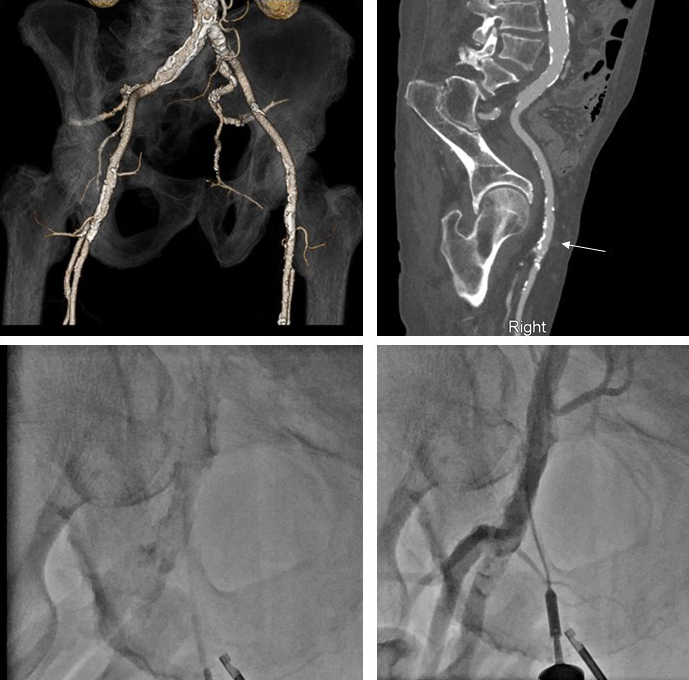

Fig. 4.Computed tomography, fluoroscopy, and femoral angiography for femoral access. (Top left panel) CTA obtained prior to TAVR notes extensive calcifications of the left and right iliofemoral system. (Top right panel) Muti-planer reconstruction of the right iliofemoral system with area of planned vascular access notated with white arrow. This area was chosen due to lack of anterior calcification. (Bottom right panel) Fluoroscopic evidence of dense calcification of the right CFA. (Bottom right panel) Femoral angiogram following TAVR procedure and deployment of 2 Proglide sutures. This was achieved by passing a micropuncture sheath over the guidewire prior to finally locking the sutures. Femoral angiogram noted patent femoral vessels without change from baseline, vascular no complications and adequate hemostasis.

Femoral access remains the predominant option for large bore arterial procedures. Slender sheaths and sheathless guides facilitate the ability to perform most procedures via the radial approach. Femoral access, however, is required for mechanical circulatory support, structural procedures such as transcatheter aortic valve replacement, and often used for chronic total occlusion (CTO) PCI in which 2 arterial access sites are needed [47]. There is emerging evidence of the safety and efficacy of bi-radial access for CTO interventions [48]. For non-emergent procedures, careful vascular access planning is a crucial component of large bore access. For TAVR it is common to obtain a CT angiogram of the vascular access options (Fig. 4). The location of vascular access can be chosen and then targeted during the case to precisely enter the CFA at the pre-planned location to decrease the risk of vascular complications (Fig. 4). Besides CT, other non-invasive imaging modalities that can inform vessel size, anatomy, and presence of peripheral arterial disease, include ultrasound, vascular non-contrast CT which allows vessel sizing and assessment of anatomy and tortuosity but not stenoses, and magnetic resonance imaging.